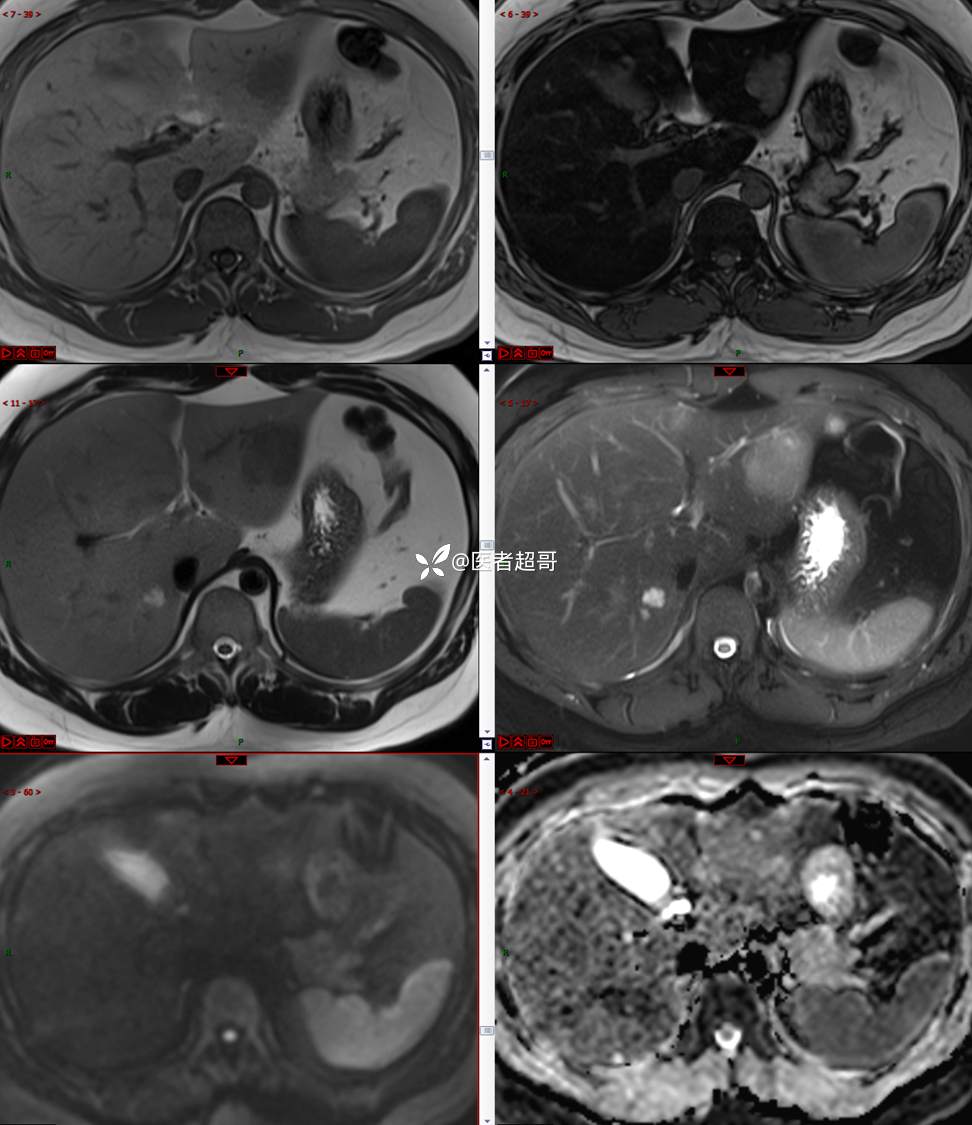

【影诊笔记685】男,31y,发现肝占位性病变5天就诊,请诊断分析,有病理结果!

主 诉:发现肝占位性病变5天。

现病史:患者缘于5天前体检时发现肝占位性病变,未予以特殊处置。现患者为求系统诊治就诊于我院,行普美显提示:肝左叶富血供占位,请结合临床及其他检查,肝多发血管瘤,脂肪肝,肝囊肿,请结合临床。门诊以“肝占位性病变”收入我科。病程中,饮食睡眠可,二便可,近期体重未见明显变化。